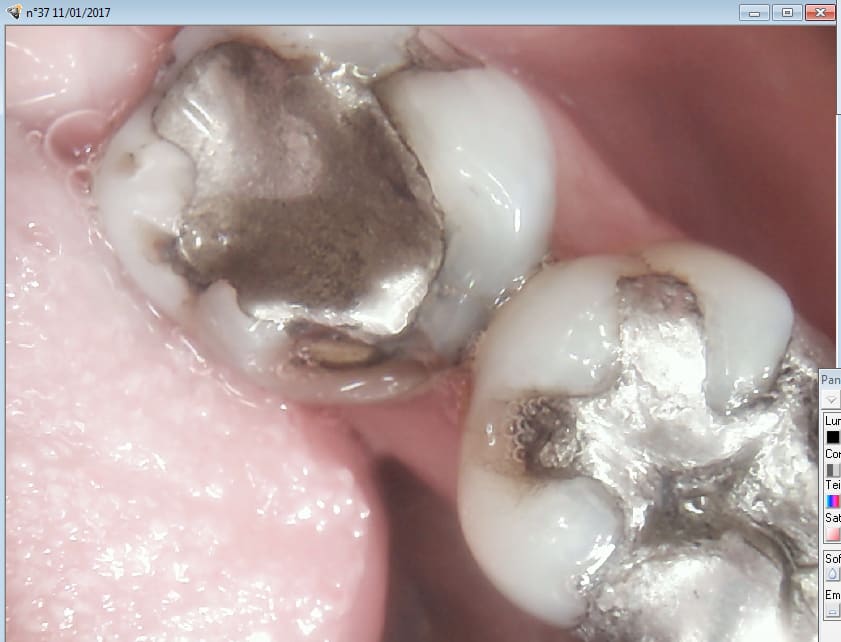

pit-être ! mais de là à m'y attaquer dès la 2ème séance alors que le gars il a gobé ses ATB en même temps que la dinde et le foie gras ... je sais pas ! ça me sctoche un peu ! et puis quand tu vois la 16 aussi ... Si quelqu'un a récupéré le patient de chicot , qu'il le lui rende SVP ! Ah oui un petit conseil de vieille branche , un AMG ça se sculpte , c'est pas pour rien qu'il y a des sillons sur une dent , ça sert pas seulement à faire joli ! ça permet aussi de répartir les forces , et d'éviter ainsi les fractures.

Mais bien sur avec des parois résiduelles de meme pas 1 mm. Ca n'est pas l'indication d'un amalgame.

Sinon je suis d'accord avec Chicot pour sa 37 : remettre un amalgame sur ça c'est risqué quand même. Un bon Overlay ou une couronne c'est plus l'indication

> Sinon je suis d'accord avec Chicot pour sa 37 : remettre un amalgame sur ça

> c'est risqué quand même. Un bon Overlay ou une couronne c'est plus l'indication

Ou une endo car l'état de la pulpe n'est pas au top après des années d'obturation volumineuse.